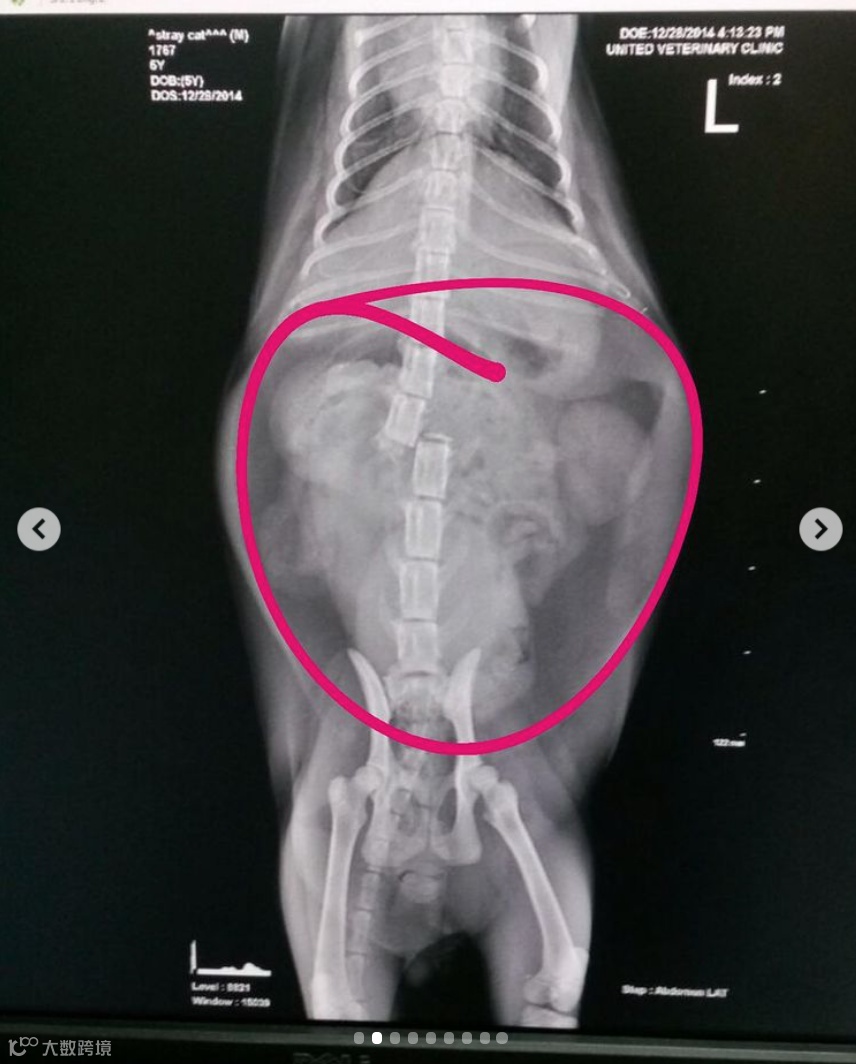

这只猫的脊椎骨折,腿部骨折,胃胀,被怀疑被锤打或绑起来踢了脚。

Chow说,早在七年前,虐待猫的案例就引起了社区的关注,当时发现了那只折断脊椎的猫。

幸运的是,这只猫在事件中幸存了下来,但此后一直存在排便困难的问题。

据Chow称,喂食器一直在通过物理刺激猫的粪便帮助猫手动排泄,并在七年后继续这样做。